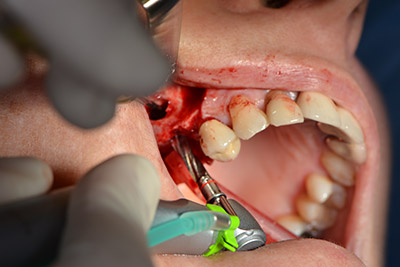

Dunque, l'impianto viene posizionato e l'osso ricostruito. In questo caso, considerate le dimensioni della regione di accrescimento, i microframmenti dell'osso autologo (raccolti con un'apposita cannula di aspirazione in seguito alla perforazione dell'impianto 16 e della fenestrazione 14) vengono combinati con dei materiali di riempimento dell'osso.

Una membrana riassorbibile viene usata come barriera in direzione buccale per contenere l'accrescimento. Infine, vengono applicate suture resistenti alla saliva (da fig. 15 a 19).